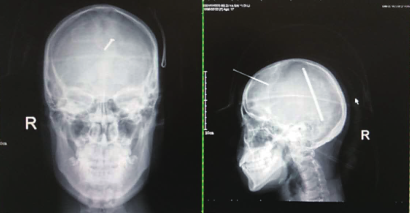

医院拍摄的脑部CT及头颅正侧位片,医院提供。

据阿克苏地区第一人民医院神经外科副主任魏建军回忆,当时阿依古丽送到急诊科后,医院为她拍摄了脑部CT及头颅正侧位片,从拍摄的片子中能够清楚看到,阿依古丽脑门正中稍微偏右的位置,扎进一根细长的物体。

“那根钢钉大约有7厘米长,穿透安全头盔后,还有4厘米刺入了患者颅内,非常危险。”魏建军介绍,医院立即对患者进行了抢救,终于在术后3小时使阿依古丽脱离了生命危险。